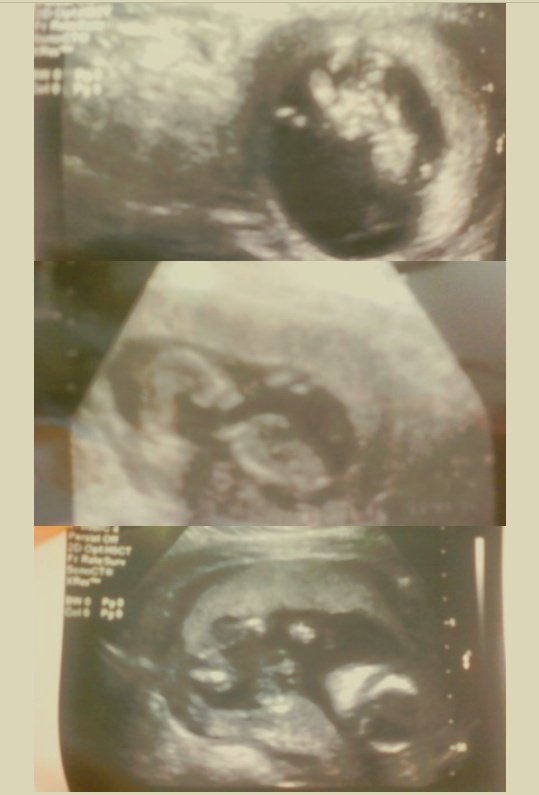

무럭무럭 잘 자라고 있는 우리아기 모습